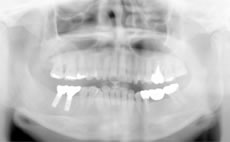

あごの骨にチタン性の人工歯根を埋め込み、噛む力を再生させる治療法です。

チタン性のインプラントは1965年にスウェーデンで開発され、日本では1996年頃から歯を失った部分の治療の選択肢としてインプラントが普及してきました。現在世界中で約100種類のインプラントがあり、日本では20種類以上のインプラントが国に認可されています。